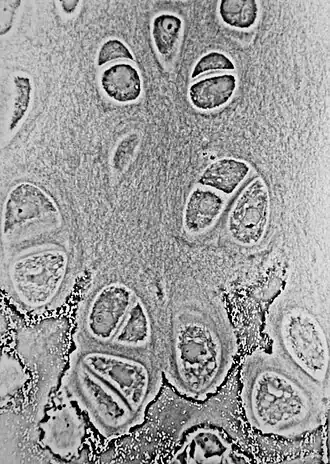

Si se observa una delgada capa bajo el microscopio, se encontrará que está formado por células con forma redondeada o sin puntas, en grupos de dos o más en una matriz biológica granular o casi homogénea. Al microscopio óptico no se observa red fibrilar en la matriz extracelular, sin embargo, al utilizar luz polarizada pueden visualizarse redes de fibrillas. Este efecto óptico se debe a que el índice de refracción de las fibrillas es similar al de la matriz en las que se encuentran inmersas.

La matriz extracelular es una red 3D muy compleja. Las células se encuentran en las cavidades de la matriz, llamada lagunas del cartílago; en torno a estas la matriz está dispuesta en líneas concéntricas, como si se hubiera formado en porciones sucesivas alrededor de las células del cartílago. Esto constituye la llamada cápsula del espacio.

Cada laguna está generalmente ocupada por una sola célula, pero durante la división de las células puede contener dos, cuatro u ocho células, lo que constituye un grupo isogénico o grupo de células isogénicas

Es característico que los condrocitos que han surgido de una célula progenitora por división mitótica se ubiquen en grupos pequeños contiguos (grupos celulares isógenos). En el entorno inmediato de las células cartilaginosas la matriz contiene glucosaminoglucanos muy sulfatados y recibe el nombre de matriz territorial. Esta matriz se tiñe de color azul violeta intenso en los preparados coloreados con H-E. El grupo de condrocitos y su matriz forman un territorio cartilaginoso (= condrona). La matriz entre los territorios se denomina matriz interterritorial. Carece de células y se tiñe de un tono pálido.

Los condrocitos están ubicados en espacios ("lagunas" o condroplastos) de la matriz cuya pared, o sea, el entorno inmediato de las células cartilaginosas también recibe el nombre de cápsula condrocítica. La región capsular con frecuencia posee una capa pericelular con función protectora especial contra la compresión y la tracción. En los preparados histológicos, los condrocitos suelen aparecer retraídos artificialmente dentro de sus lagunas.